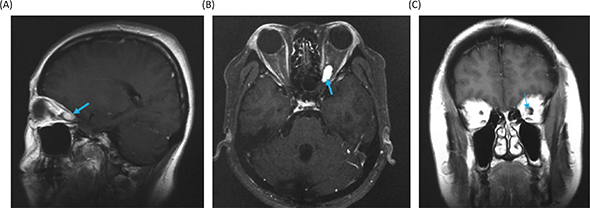

Magnetic resonance imaging (MRI) of the head showed a Gd-enhanced well-circumscribed mass on the left retrobulbar optic nerve in the orbital, and three-dimensional MRI showed the tumor enveloped the left optic nerve (Figure 4).

Figure 4. Magnetic resonance images before radiosurgery. (A) Gadolinium (Gd)-enhanced T1-weighted image, sagittal. (B) Gd-enhanced T1-weighted image, axial. (C) Gd-enhanced T1-weighted image, coronal. Yellow arrows show the tumor. (D) Three-dimensional planning MRI for radiosurgery. The light blue color indicates the tumor enveloping the optic nerve.